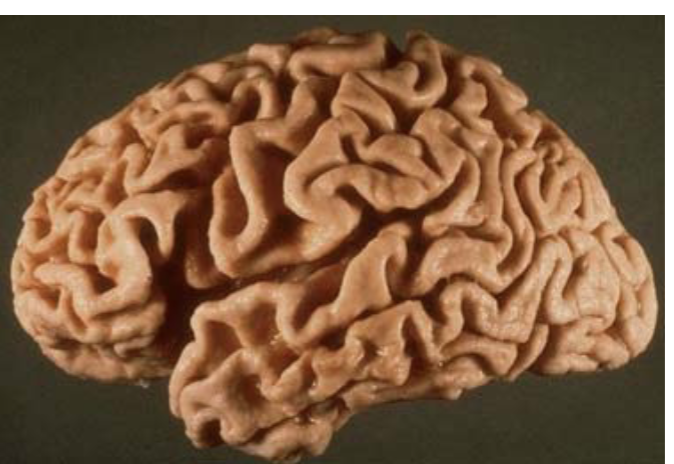

What pathology is shown in the provided image?

Cortical atrophy (consistent with Alzheimer disease)